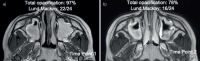

Example T2-weighted magnetic resonance images in a 6-year-old with chronic rhinosinusitis. a) Time point 1 of axial image. b) Time point 2 of axial image obtained 6 months later.